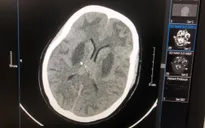

Bác sĩ Nguyên đánh giá mức độ tổn thương não của bệnh nhân ngộ độc methanol. Ảnh: BVCC